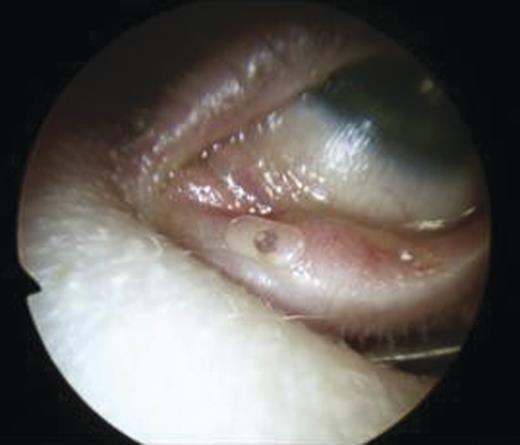

- An inferiorly based mucosal flap was elevated on the lateral nasal wall (Fig. 8) with the incision performed using a small myotome.

Removal of part of the lateral nasal wall anterior to uncinate process was performed for access to the lacrimal system (unciformian endonasal DCR)

30° punch forceps were used to nibble bone sequentially for adequate exposure.

Further drilling of the lateral bony wall was undertaken with a small cutting burr.